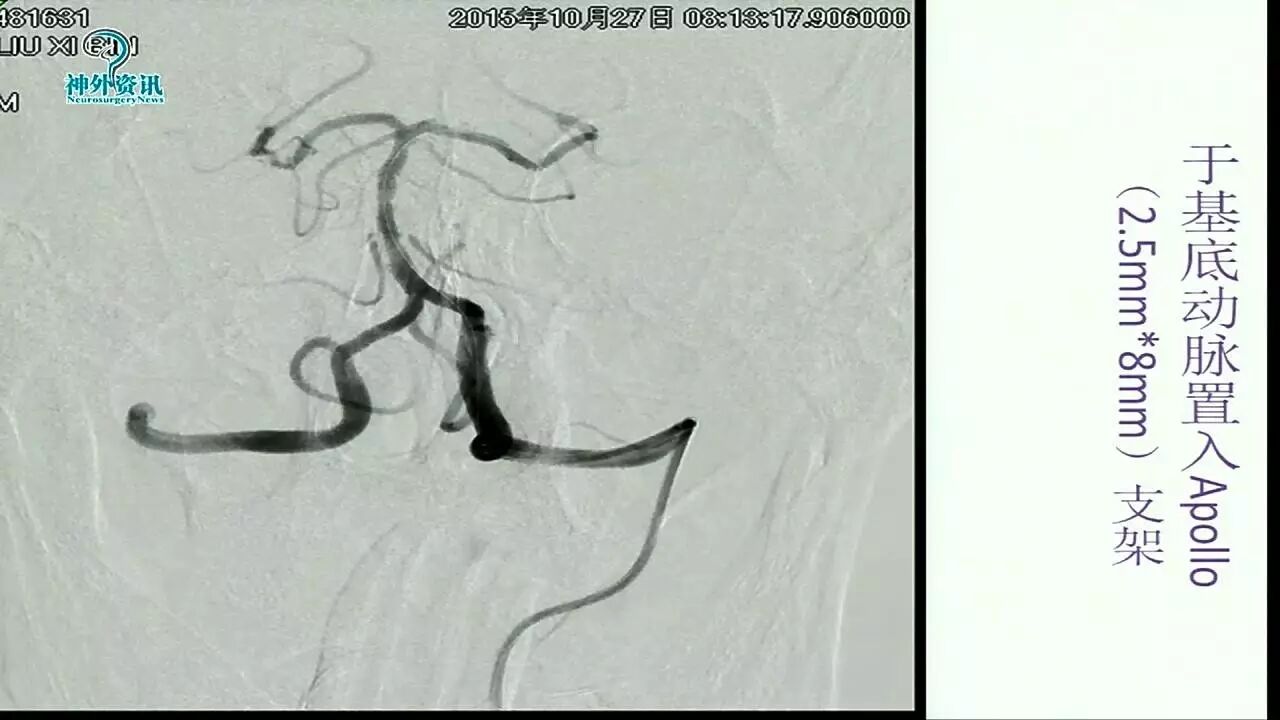

Enterprise支架在缺血性脑血管病中的应用